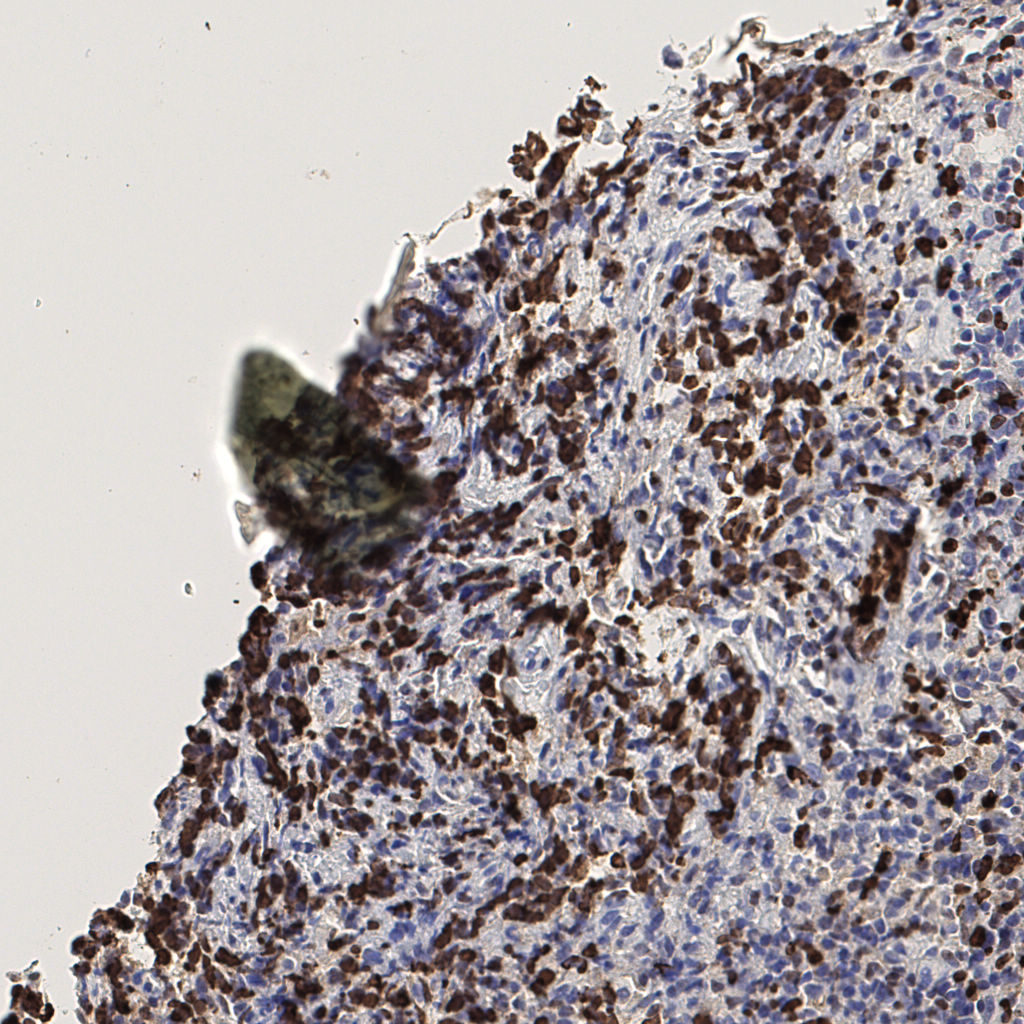

7.85%

Ki67 指数

阴 1104 阳 94